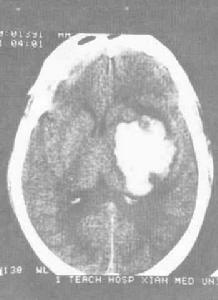

檢查:腦CT、磁共振掃描。

中老年高血壓患者在活動或情緒激動時突然發病,迅速出現偏癱、失語等局灶性神經功能缺失症狀,以及嚴重頭痛、惡徒及意識障礙等,常高度提示腦出血可能,CT檢查可以確診。